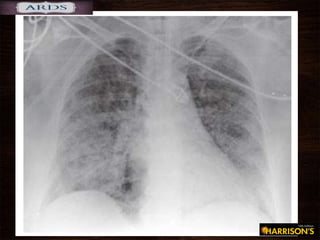

• #41 A representative anteroposterior chest x-ray in the exudative phase of ARDS shows diffuse interstitial and alveolar infiltrates that can be difficult to distinguish from left ventricular failure.

• #40  In addition, condensed plasma proteins aggregate in the air spaces with cellular debris and dysfunctional pulmonary surfactant to form hyaline membrane whorls. Pulmonary vascular injury also occurs early in ARDS, with vascular obliteration by microthrombi and fibrocellular proliferation (Fig. 322-3). Alveolar edema predominantly involves dependent portions of the lung, with diminished aeration and atelectasis. Collapse of large sections of dependent lung markedly decreases lung compliance. Consequently, intrapulmonary shunting and hypoxemia develop and the work of breathing increases, leading to dyspnea. The pathophysiologic alterations in alveolar spaces are exacerbated by microvascular occlusion that results in reductions in pulmonary arterial blood flow to ventilated portions of the lung (and thus in increased dead space) and in pulmonary hypertension. Thus, in addition to severe hypoxemia, hypercapnia secondary to an increase in pulmonary dead space is prominent in early ARDS. The exudative phase encompasses the first 7 days of illness after exposure to a precipitating ARDS risk factor, with the patient experiencing the onset of respiratory symptoms. Although usually presenting within 12–36 h after the initial insult, symptoms can be delayed by 5–7 days. Dyspnea develops, with a sensation of rapid shallow breathing and an inability to get enough air. Tachypnea and increased work of breathing result frequently in respiratory fatigue and ultimately in respiratory failure. Laboratory values are generally nonspecific and are primarily indicative of underlying clinical disorders. The chest radiograph usually reveals alveolar and interstitial opacities involving at least three-quarters of the lung fields. While characteristic for ARDS, these radiographic findings are not specific and can be indistinguishable from cardiogenic pulmonary edema (Chap. 326). Unlike the latter, however, the chest x-ray in ARDS rarely shows cardiomegaly, pleural effusions, or pulmonary vascular redistribution. Chest CT in ARDS reveals extensive heterogeneity of lung involvement Because the early features of ARDS are nonspecific, alternative diagnoses must be considered. In the differential diagnosis of ARDS, the most common disorders are cardiogenic pulmonary edema, diffusepneumonia, and alveolar hemorrhage. Less common diagnoses to consider include acute interstitial lung diseases (e.g., acute interstitial pneumonitis; Chap. 315), acute immunologic injury (e.g., hypersensitivity pneumonitis; Chap. 310), toxin injury (e.g., radiation pneumonitis; Chap. 263), and neurogenic pulmonary edema (Chap. 47e).